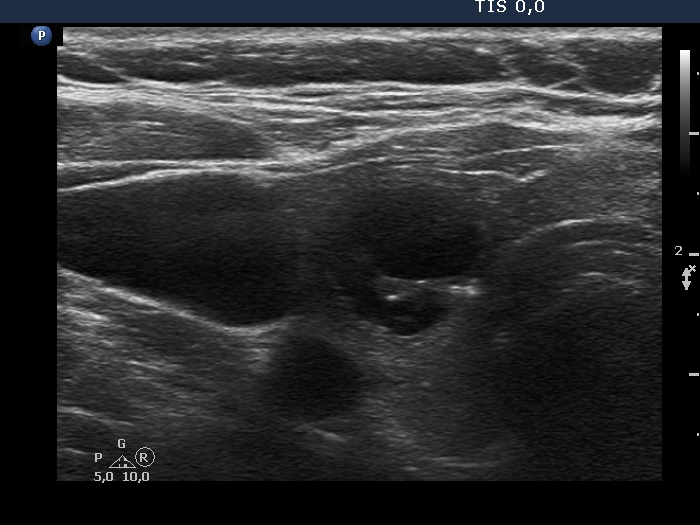

Examination in 2018 (second row of images):

Clinical data. The patient came to a routine follow-up. She had no complaints.

Palpation: unchanged.

Laboratory test: TSH 0.36 mIU/L on daily 125 microgram levothyroxine.

Ultrasonography. Except for the lesion which was previosuly cytologically investigated, the pattern remained unchanged. The lesion in question became cystic and was composed of two chambers. In the tissue part separating the two chambers, hyperechoic granules have appeared. These were mostly related to ventral cystic areas, therefore, they should be regarded as back wall figures.

We recommended that she takes the replacement therapy at the same dose and has a TSH scan after half a year and an ultrasound scan after two years.